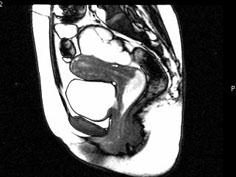

问题 女,28岁,阴道有异常液体流下,CT和MRI扫描如图,下列说诊断正确的是 ( )

选项 A、考虑为左侧输尿管异位开口 B、考虑为膀胱阴道瘘 C、MRI的T2加权像示宫颈阴道内有大片状高信号影 D、膀胱后下缘可见鸟嘴状突起 E、CT增强示造影剂由膀胱进入阴道

答案 BCDE